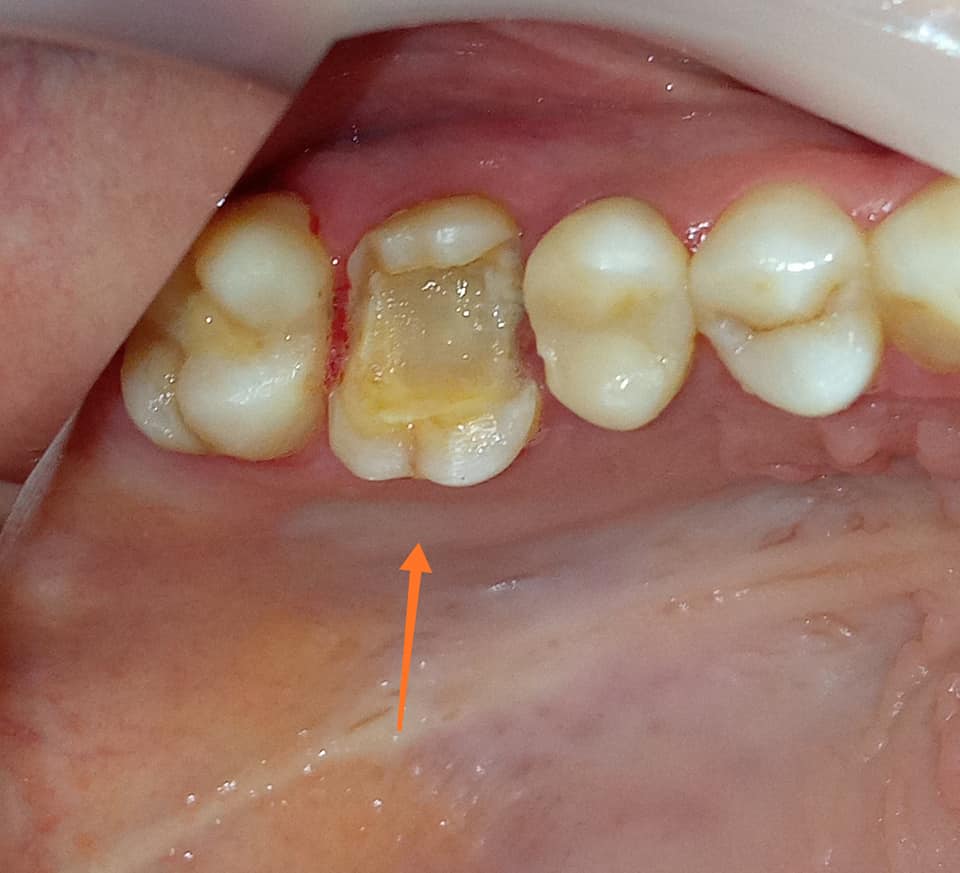

Αρχική κλινική εικόνα του παλιού σπασμένου σφραγίσματος

Εικόνα του δοντιού πριν τη λήψη αποτυπώματος